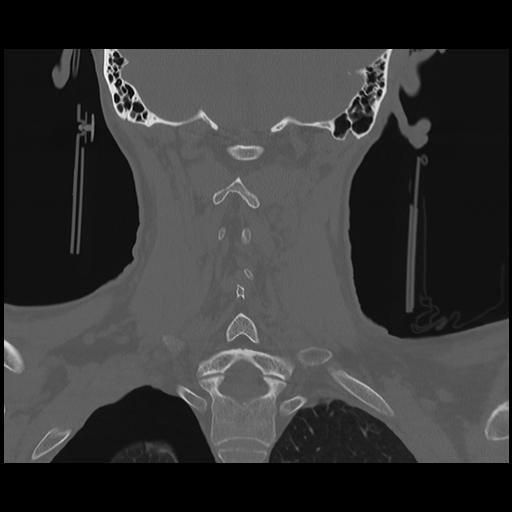

16 HUESO,,Coronal,2.000,HUESO,Coronal,